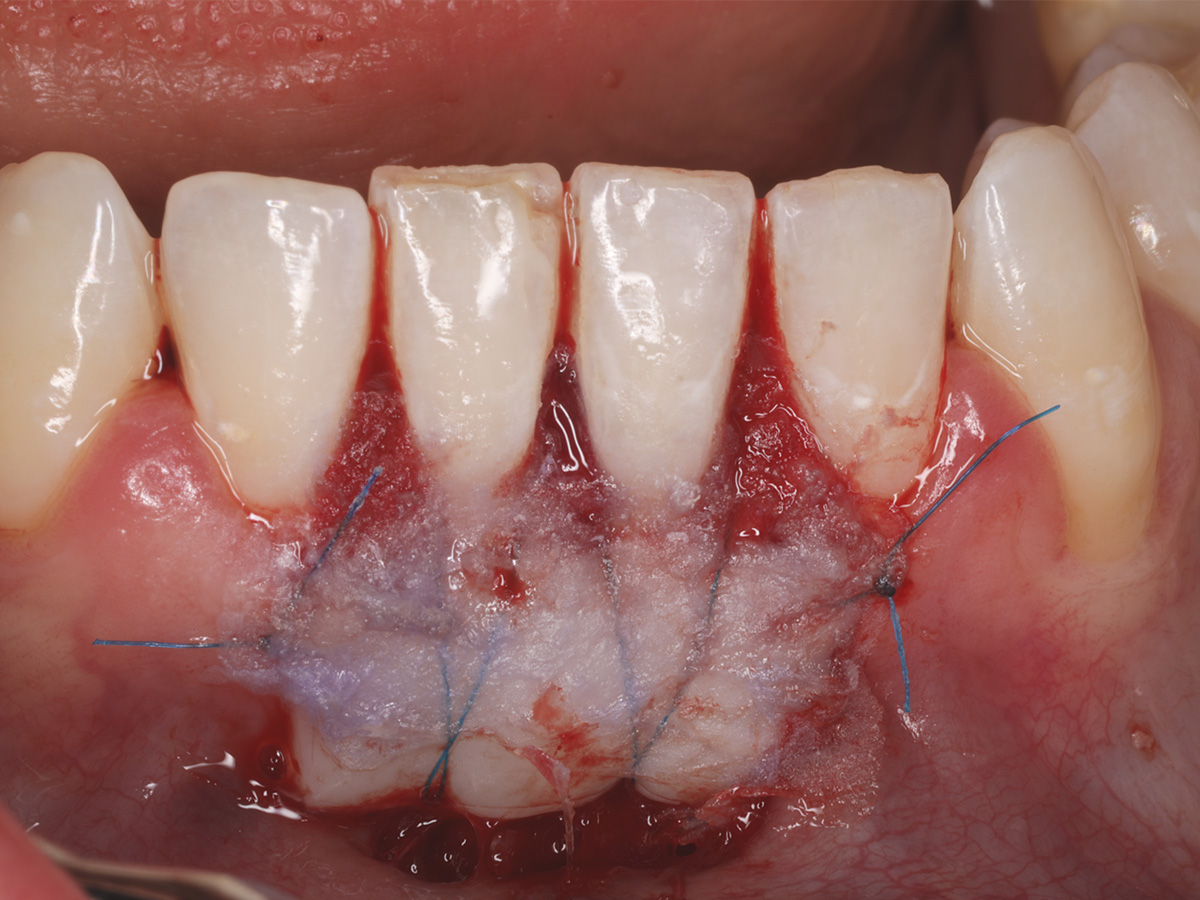

Abbildung 4

Abdeckung des Transplantates mit PeriAcryl® 90-HV Gewebekleber.